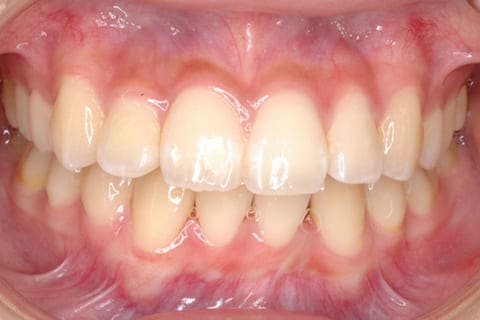

歯並びが気になる

Dentition

凸凹・乱ぐい歯・出っ歯・すきっ歯などの歯並びに関する症状でお悩みの方へ

健康に美しく臨床実績集

虫歯や歯周病、事故などでの欠損、

噛めるようになりたい、見た目の美しさの追求など、

審美的に機能的に回復した治療経過報告症例です。